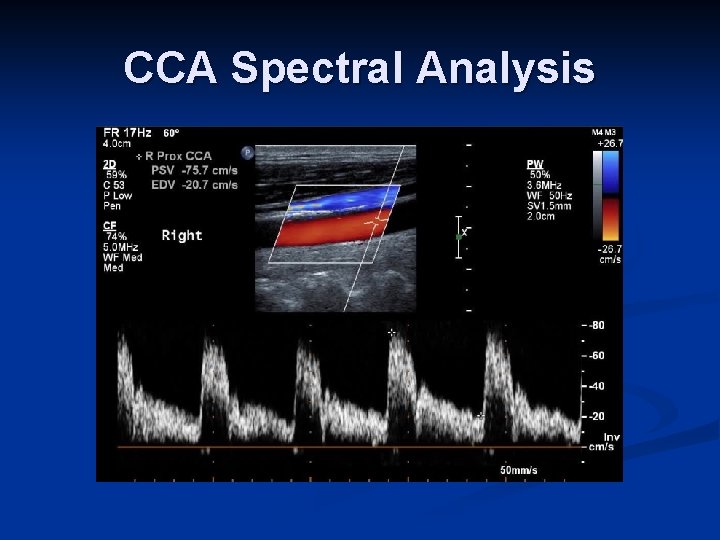

Carotid Ultrasound Evaluation Spectral Analysis Graphic display of velocities and direction of moving red blood cells in the sample volume n X axis, Y axis n Direction of flow n Amplitude of “velocity component” (# of RBCs within each velocity component = brightness of the trace) n Spectral window – black zone between baseline and spectral line n

CCA Spectral Analysis

Carotid Ultrasound ECA – feeds high resistance vascular bed; velocity rises sharply during systole, falls quickly during diastole n ICA – feeds lower resistance brain circulation; large quantities of flow continue during diastole; supplies brain; velocities usually increase from prox to distal n CCA – resembles ICA waveform, with diastolic flow above the baseline n